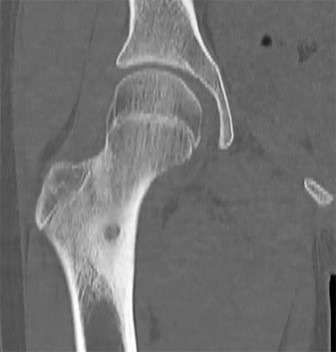

A 13-year-old obese male with a stable left Slipped Capital Femoral Epiphysis (SCFE) undergoes in situ pinning with a single cannulated screw.

Six months postoperatively, he develops severe, constant hip pain and a significantly restricted range of motion in all planes. Radiographs demonstrate concentric joint space narrowing without hardware failure. What is the most likely diagnosis?

A 12-year-old obese male presents with severe left hip pain and is completely unable to bear weight, even with the assistance of crutches. Radiographs confirm a severe left Slipped Capital Femoral Epiphysis (SCFE). Which of the following best describes his classification and the associated risk of the most catastrophic complication?

Explanation

Question 44

A 12-year-old boy with a BMI in the 99th percentile presents with left knee pain and an inability to bear weight on his left leg. Radiographs confirm a severe Slipped Capital Femoral Epiphysis (SCFE). Which of the following factors is the greatest predictor for the development of avascular necrosis (AVN) in this patient?

Question 60

A 12-year-old boy presents with a 3-week history of right hip pain and a limp. He is unable to bear weight on the right leg, even with crutches. Radiographs confirm a Slipped Capital Femoral Epiphysis (SCFE). According to the Loder classification, what is the most significant prognostic factor associated with this specific presentation?